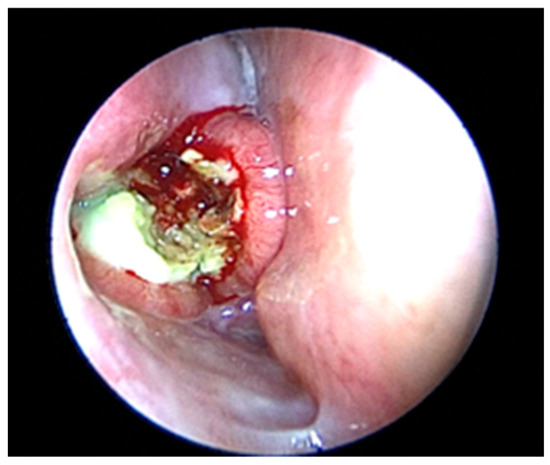

2. Case Presentation